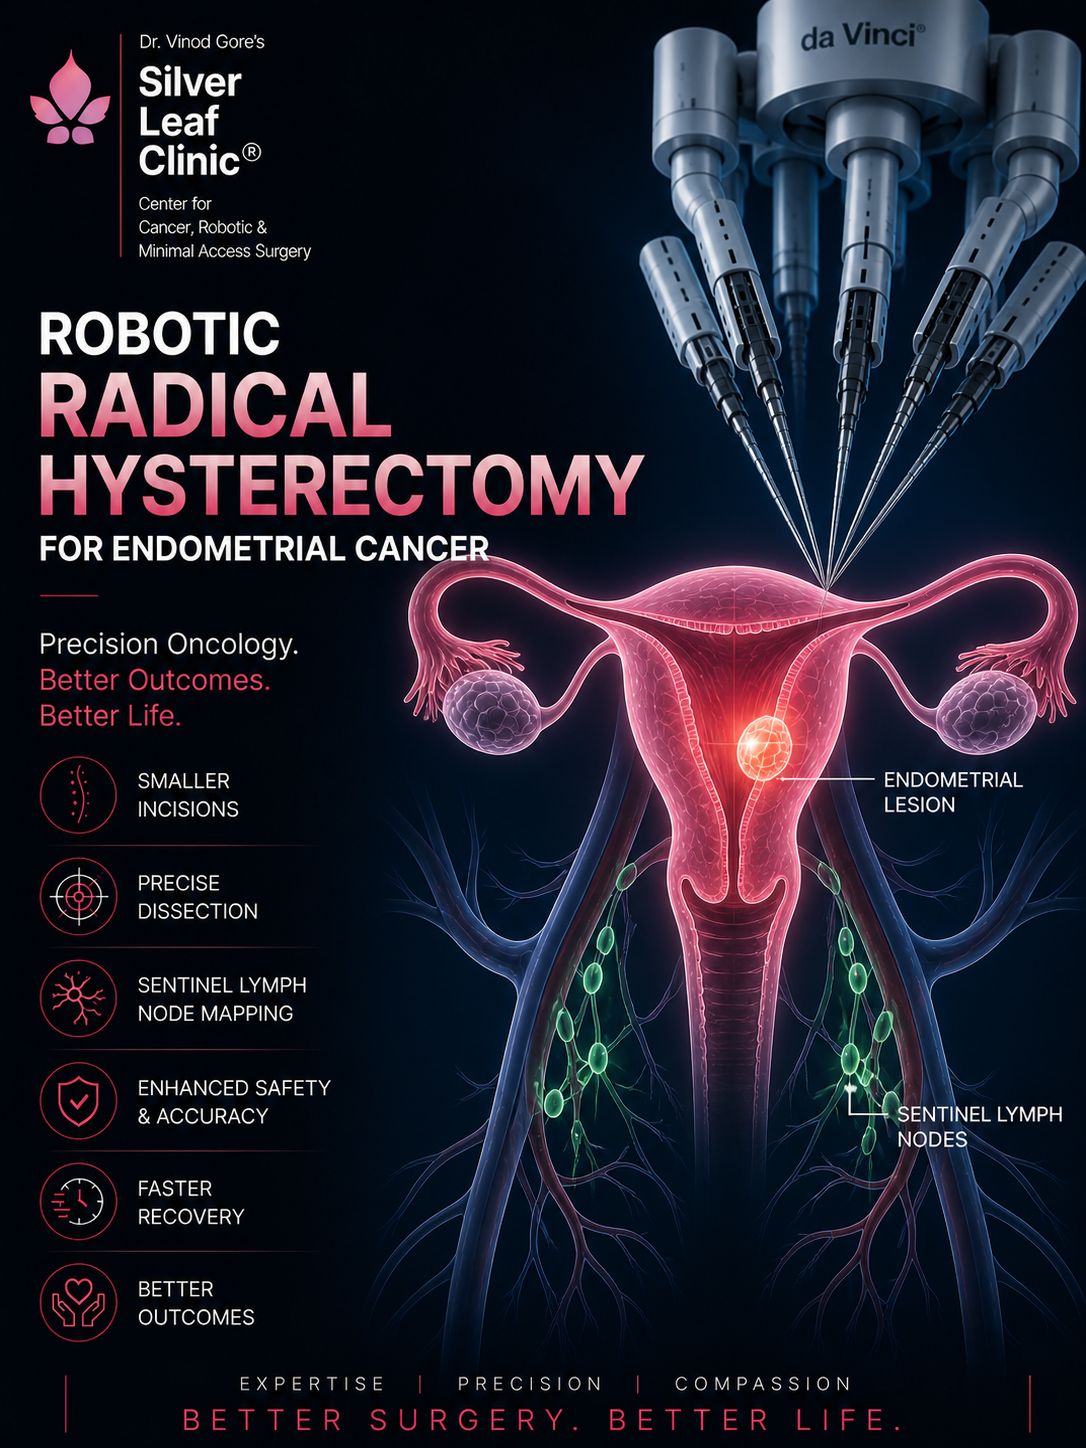

Dr. Vinod T. Gore is a senior surgical oncologist with nearly three decades of experience in advanced cancer surgery, robotic oncosurgery, and complex oncologic procedures. He currently serves as Department Head, Surgical Oncology at Sahyadri Manipal Hospital, Pune — a position he has held since the department's inception in 2009, having played a pioneering role in building its surgical oncology and robotic surgery capabilities from the ground up.

He is internationally trained in advanced robotic surgical techniques, holding the Fellowship in Advanced Robotic and Innovative Surgery (FARIS) from the University of Edinburgh. His robotic programme at Sahyadri Manipal Hospital is a designated Robotic Surgery Centre of Excellence and serves as an accredited FARIS training centre — where Dr. Gore mentors and trains surgical oncology fellows in advanced robotic procedures. These are two distinct and separate recognitions.